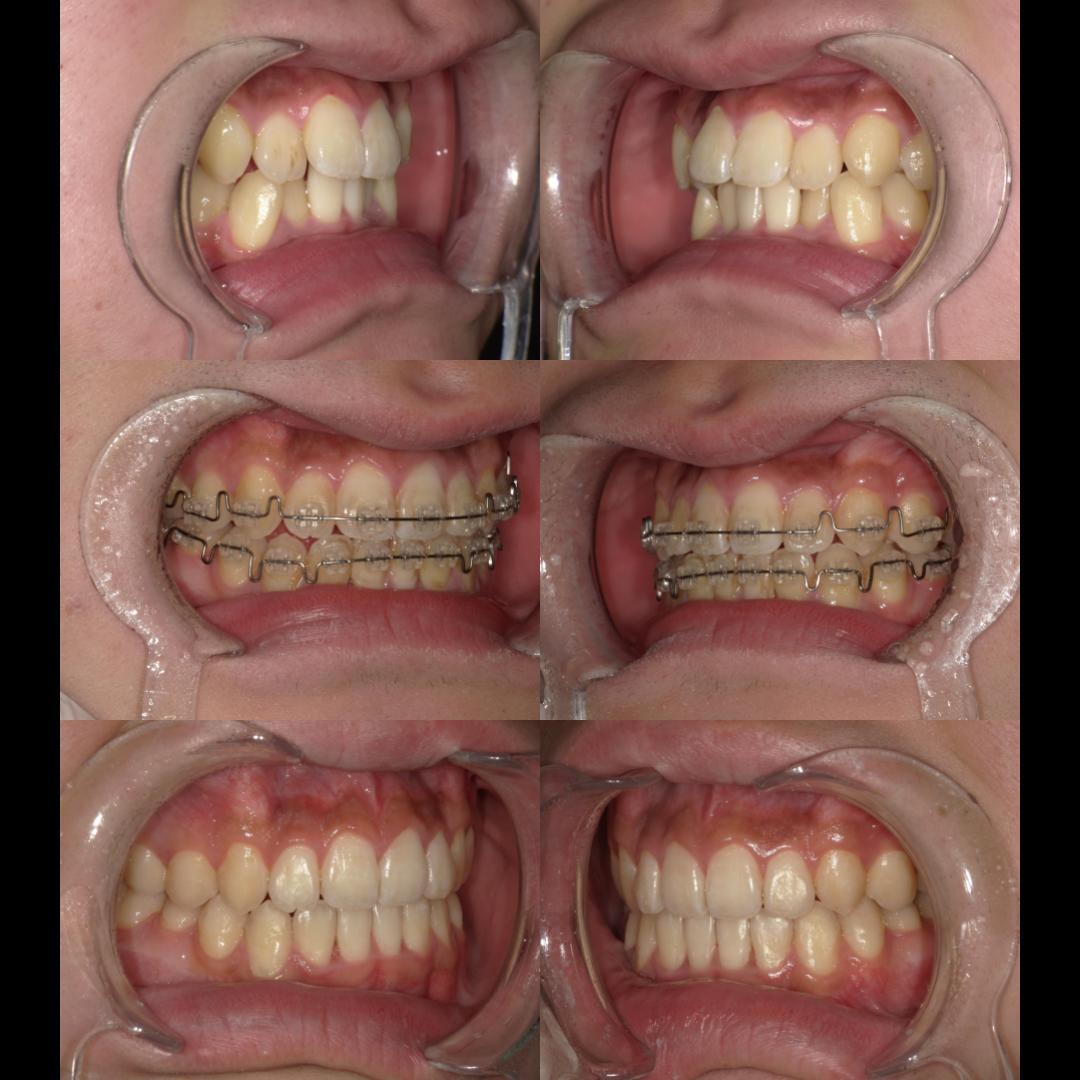

現在、歯列不正になる原因は、下顎の位置関係、歯の傾きなど様々な要因があることがわかっています。

そういった様々な要因を取り除くことで、従来、小臼歯(4番、5番)を抜歯しなければ治療できない症例でも、非抜歯で治療可能となってきているのです。

機能的に小臼歯は非常に大切な歯であることから、最大限小臼歯を抜歯せずに治療できる治療方針を考えます。

また、下顎の位置関係、歯の傾きなどの原因を新素材ゴムメタルワイヤーで治療を行うことでほとんどの症例で小臼歯を抜歯しなくても治療可能になってきています。